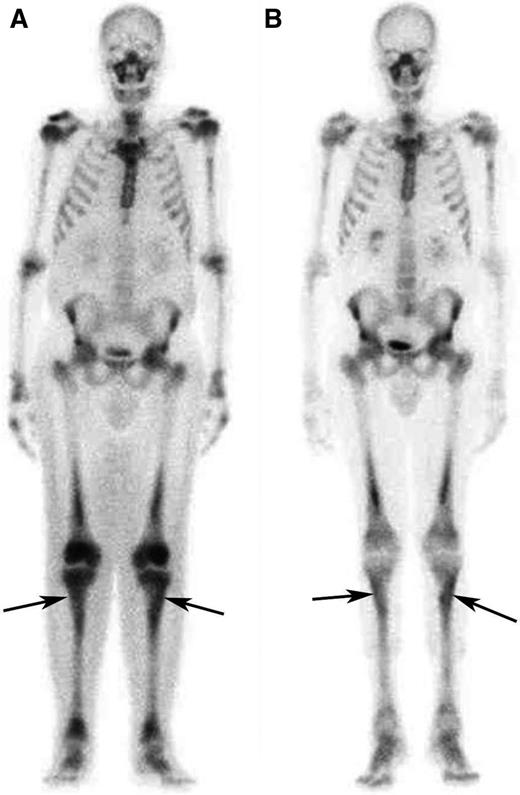

Response to treatment in the long bones assessed by bone scintigraphy. (A) Whole-body 99Tc-bone scintigraphy performed before treatment and (B) after 12 months of treatment with SRL and PDN in patient #5. The scans show a significant reduction in tracer uptake especially in long bones such as the tibias (arrows) and the femurs.